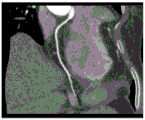

FIG. 8 is a diagram of the coronary probe generated;

The coronary artery probe generation module takes the central line of each blood vessel and the original image sequence as input, reconstructs the original image sequence into body data, cuts the body data along the vertical direction of the tangent lines of two adjacent points of the central line in the body data to obtain a cut plane, cuts out an image with fixed size by taking the coordinate of the corresponding central line point on the cut plane as the center, and obtains the coronary artery probe image. Fig. 8 shows the generated coronary probe map.